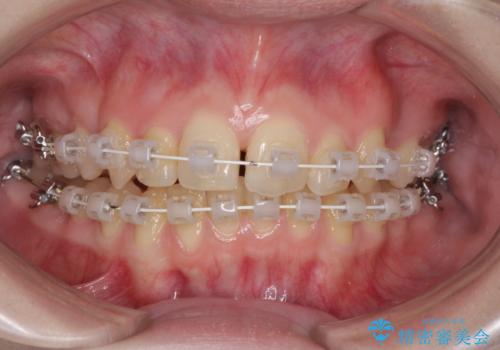

- 矯正装置

- 審美装置

- 治療期間

- 1年6ヶ月